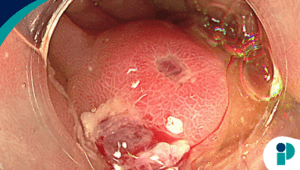

La EoE (por sus siglas en inglés) es una enfermedad inflamatoria crónica del esófago, mediada por eosinófilos y con componente alérgico, que afecta especialmente a población pediátrica. Se presenta con disfagia, dolor torácico y síntomas tipo reflujo que no responden a tratamiento convencional, lo que puede retrasar su diagnóstico.

“A nivel mundial, se estima que cerca de 1 de cada 700 personas presenta esta enfermedad”, explica la gastroenteróloga. El diagnóstico se confirma mediante endoscopia con biopsia, donde se identifican eosinófilos en el tejido esofágico.